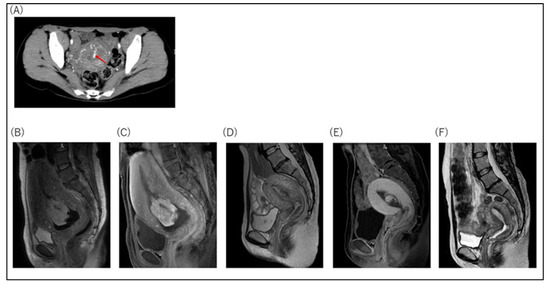

| RPOC with flow on MRI or CT, n (%) | 9/12 (75.0) | 8/9 (88.9) | 1 |